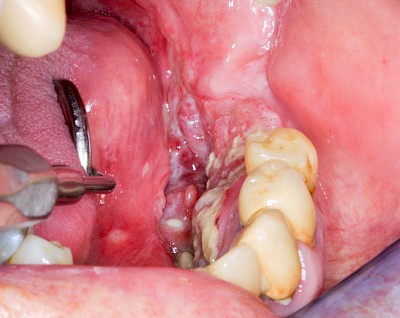

Schwellung mit Eiter: Abszess

Schwellungen im Zusammenhang mit akuten Entzündungen im Bereich der Zähne oder dem Zahnhalteapparat entstehen meist aufgrund schneller und starker Vermehrung von Bakterien sowie einer starken Abwehrreaktion des Körpers (Abszess). Diese Schwellungen entstehen meist in sehr kurzer Zeit – innerhalb von Stunden oder wenigen Tagen. Die Schwellungen sind sehr schmerzhaft. Nah am Zahnfleisch kann sich bei leichtem Druck auf die Schwellung Eiter entleeren. Mitunter fühlen sich die Menschen krank. In fortgeschrittenem Stadium kann auch Fieber auftreten. Hier ist sofort der Zahnarzt zu kontaktieren, um eine weitere Ausbreitung der Entzündung zu verhindern.